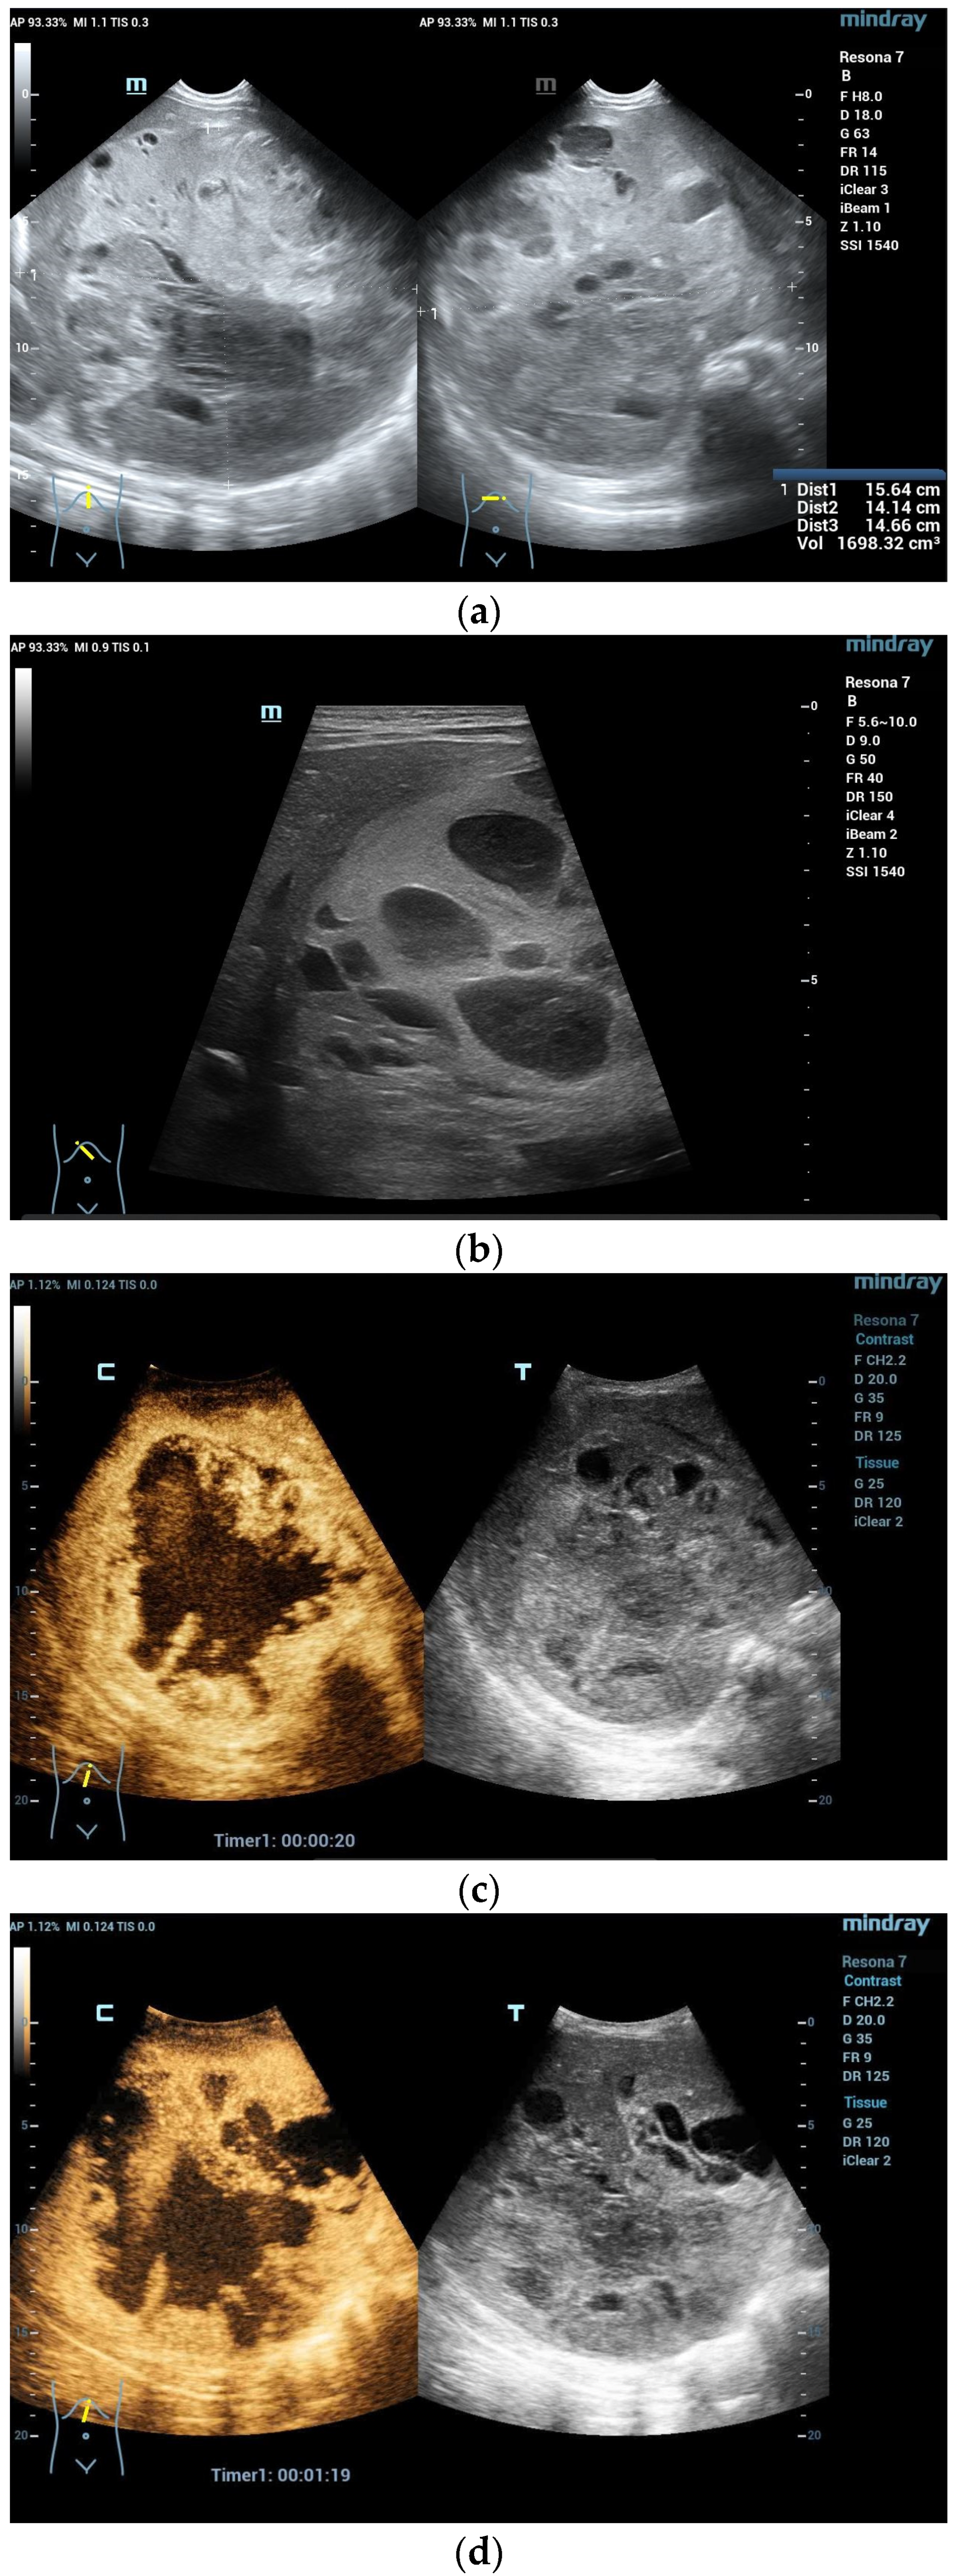

Figure 3.

Hemangioendothelioma in a 1-month-old infant. A cystic mass with a maximum diameter of 4 cm in liver segment IV with blurred borders and calcifications with dorsal acoustic shadow (a–e). Evidence of increased vascularization on color Doppler (f). Feeder artery with inflow from the hepatic artery and venous outflow via the markedly dilated left hepatic vein (g). Increased flow velocities in the coeliac trunk and hepatic artery (h,i). Outflowing left hepatic vein with arterialized flow profile and increased flow velocities (j).